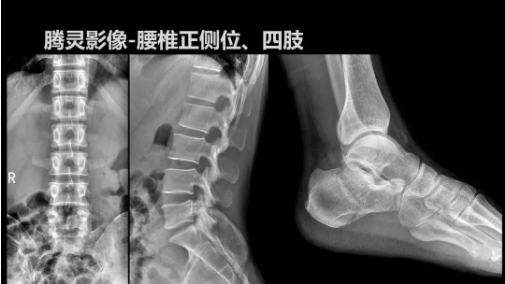

“騰靈”是安健科技的第四代動態(tài)DR產(chǎn)品,可實現(xiàn)全科室應(yīng)用。如各類常規(guī)的X線檢查、消化道檢查、骨科檢查、婦科、兒科檢查等。此外,安健科技為“騰靈”在真正意義上實現(xiàn)多科室、多功能診斷進行了多項針對性設(shè)計。

相較前代產(chǎn)品,“騰靈”在圖像質(zhì)量方面得到了全面升級,“騰靈”采用17*17非晶硅平板探測器設(shè)計,采集矩陣達3072*3072,動態(tài)范圍達16bit,為成像提供超大視野的同時保證成像質(zhì)量,此外,該款機型可根據(jù)醫(yī)療機構(gòu)的差異化需求而選配不同的動態(tài)平板探測器,以此來適應(yīng)不同階層用戶所需。